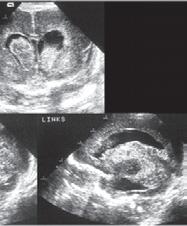

1.6.5 Krvácení do mozku (intrakraniální krvácení)

n Definice

Krvácení do mozku je častou komplikací u nedonošených novorozenců, které může vést ke vzniku hydrocefalu a k dlouhodobým neurologickým postižením.

n Epidemiologie